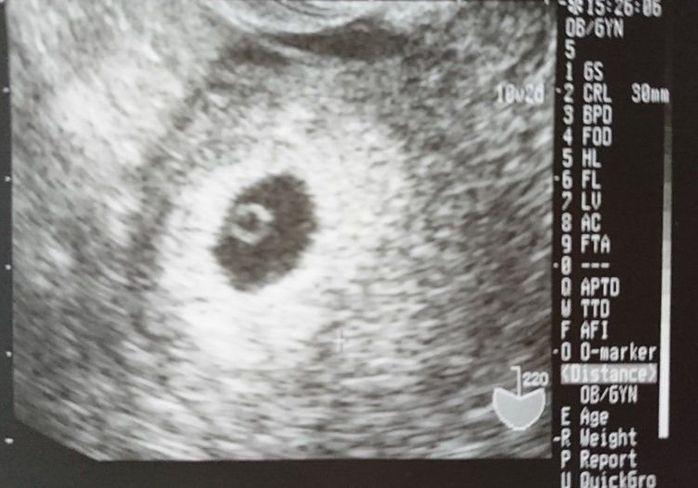

妊娠6週目のエコー写真

12月27日、妊娠したかどうか、モヤモヤした気持ちで年を越したくなかったので、検査に行きました。妊娠が分かった時は、お姉ちゃんと5歳も離れていたので、本当に嬉しかったです。サンタさんに少し遅れたクリスマスプレゼントをもらったような気がしました。赤ちゃんの袋の中に卵黄嚢が見えました。